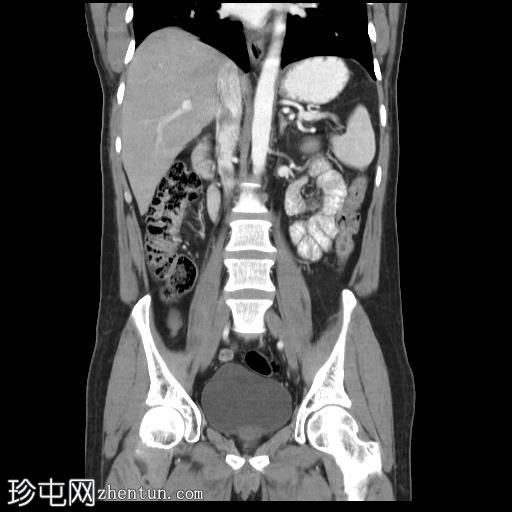

冠状位增强扫描(口服造影剂)

CT扫描显示胰腺组织完全包绕十二指肠第二段。未发现胰周结节或肿块。

环状胰腺是一种形态学异常,其特征是胰腺组织完全或部分环绕十二指肠第二段。这种情况可导致十二指肠梗阻,因此放射科医生识别此病至关重要,因为他们通常是第一个提出诊断的医生。